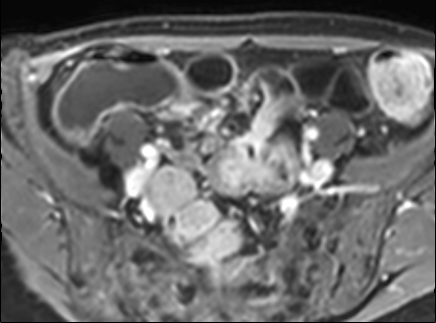

Rò

Đường xoang và đường rò là các biến chứng thường gặp ở bệnh nhân mắc bệnh Crohn.

Cả hai đều ngấm thuốc rõ rệt trên chuỗi xung T1W sau tiêm gadolinium.

Đường rò có thể biểu hiện dưới dạng cấu trúc phân lớp kiểu ‘đường ray tàu hỏa’ hoặc như một cấu trúc tuyến tính ngấm thuốc.

Đường rò có thể đi từ quai ruột này sang quai ruột khác, đến một tạng rỗng khác hoặc ra da.